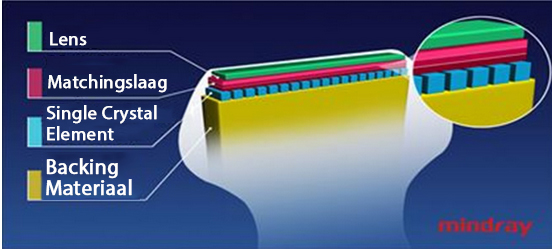

3T Transducer Technology met Single Crystal

Alle M9-compatibele sondes zijn voorzien van MindrayŌĆÖs unieke 3T transducertechnologie wat scherpere beelden oplevert. M9 maakt gebruik van monokristaltechnologie, hetgeen zorgt voor betere penetratie en betere dynamische stroming in kleur, vooral van voordeel bij het scannen van moeilijke pati?nten.